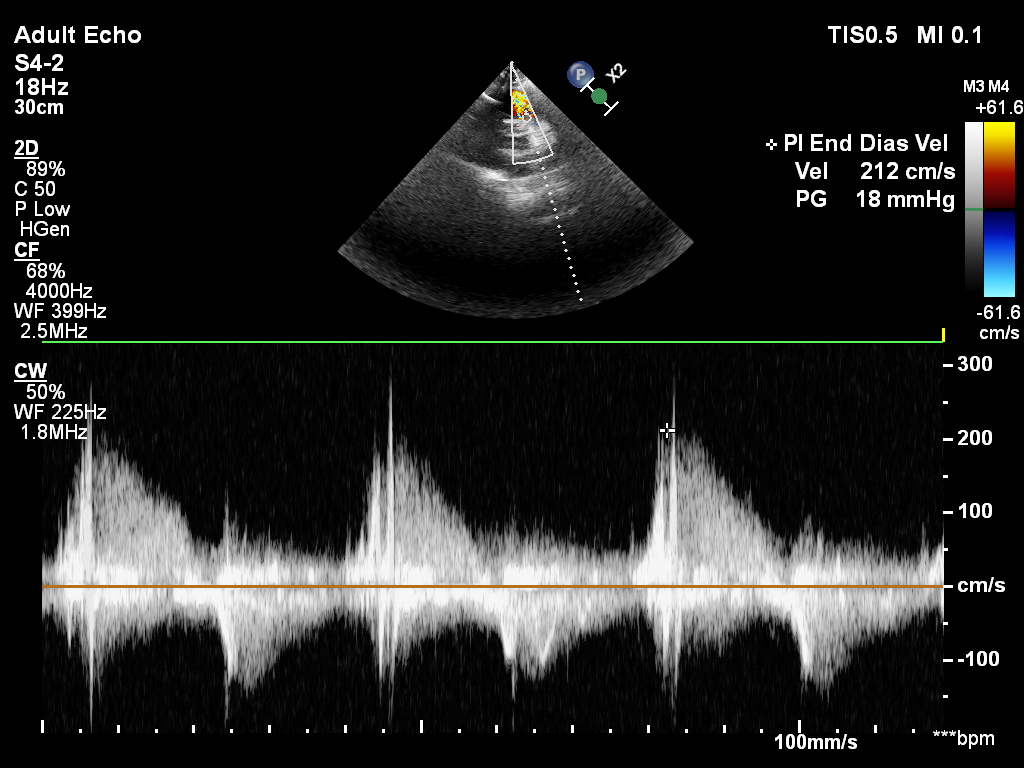

ciężka niedomykalność płucna w projekcji podmostkowej

CW Doppler przez zastawkę pnia płucnego – szybki spadek pędkości fali zwrotnej wskazuje na ciężką niedomykalność płucną